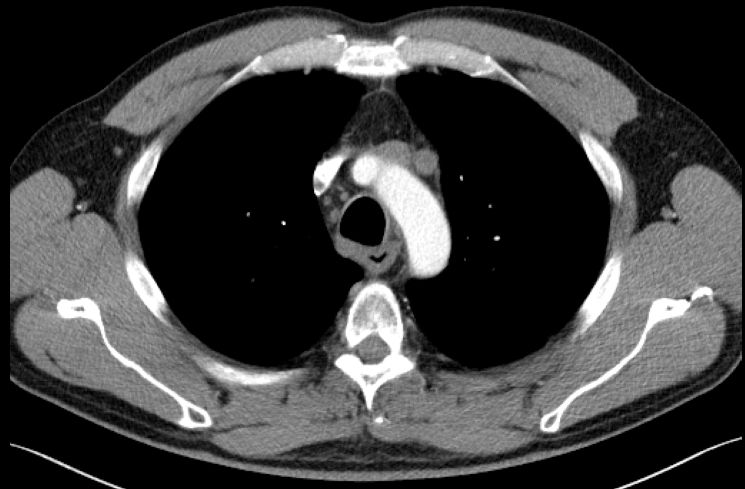

Rezidiv nach Radiochemotherapie eines kleinzelligen Tracheakarzinoms mit großer supraclavikulärer Metastase | |||